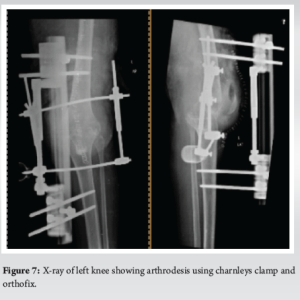

Three months after her second surgery, the patient presented with a deformity on the left side, which was diagnosed as an atraumatic posterior knee dislocation (Fig. 6). The right side was normal but stiff. Immediate reduction was performed under sedation in the operating room, followed by immobilization using an above-knee plaster slab with side support. A periprosthetic joint infection workup was conducted. The patient had a UTI due to a catheter inserted by a local physician, and her blood tests showed low hemoglobin levels of 6 g%. She was treated with intravenous antibiotics and blood transfusion. Comprehensive neurological and hormonal evaluations revealed late-onset Parkinson’s disease with Alzheimer’s traits. Follow-up X-rays indicated an unstable left knee, for which revision with a constrained implant was recommended. However, due to financial constraints and the patient’s uncooperative nature, knee arthrodesis using a Charnley clamp and Ortho fix was chosen to address the unstable left knee dislocation. During the procedure, no signs of infection were observed, but hamstring tightness was noted. The surgical team thoroughly cleaned the area with pulse lavage, removed the implant, freshened the edges, and achieved arthrodesis (Fig. 7). The infection work up did not yield result. At the 3-month follow-up, the patient had a pain-free, arthrosed left knee and a stable right knee with a range of motion from 5° to 100°, without any neuromuscular deficits (Fig. 8).